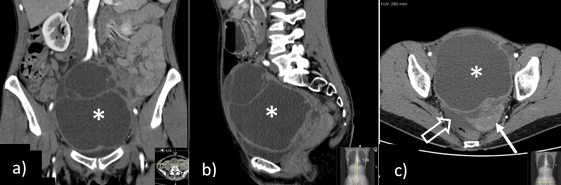

A 49-year-old woman presented to the emergency department with acute lower abdominal and pelvic pain, nausea and vomiting. Laboratory tests were unremarkable apart from a slight increase in the creatinine levels, and a CT scan was performed (Fig. 2), showing a large cystic left adnexal mass with 16 x 12 cm, causing extrinsic compression of the left ureter with mild ureterohydronephrosis, and a small amount of ascites, with no further alterations. The patient was discharged with the presumptive diagnosis of an ovarian tumour suspicious for malignancy with probable peritoneal carcinomatosis and was therefore referred to our oncology centre.

Figure 2: Coronal (a), sagittal (b) and axial (c) contrast-enhanced abdominopelvic CT shows a pelvic midline multiloculated cystic tumour, with thickened wall and non-enhancing content, thought to arise from the left adnexa (a right normal ovary was identified - not shown). Also noted, ipsilateral (left) deviation of the uterus (→) and free intra-peritoneal pelvic fluid (open arrow).